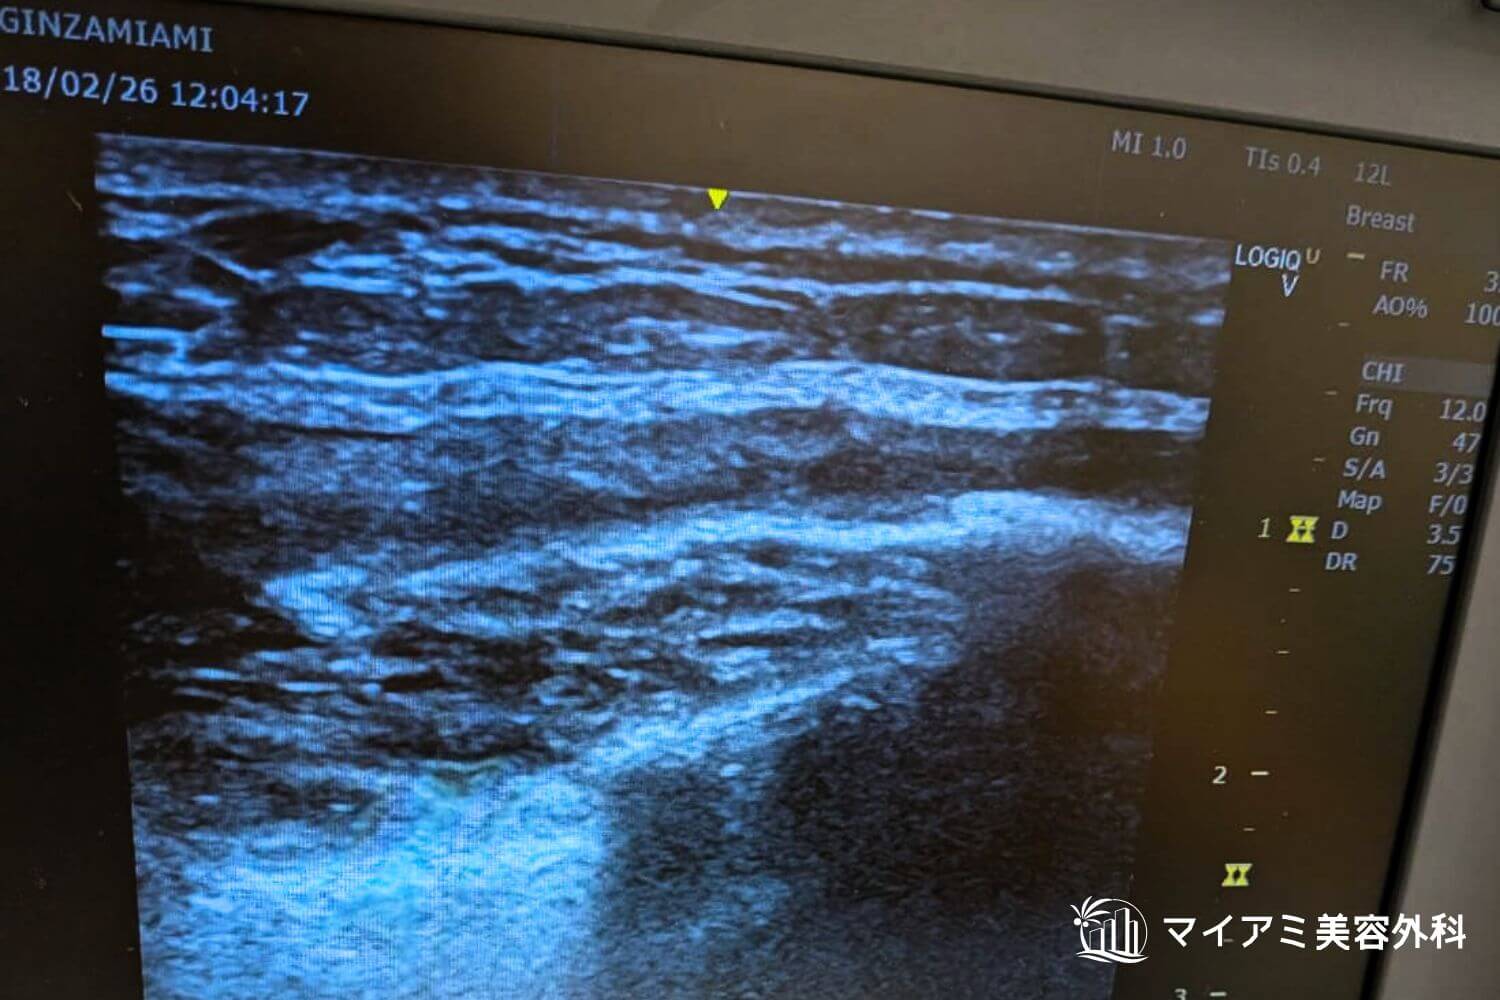

アクアフィリング除去を成功させるためには、製剤がどこに、どの程度広がっているかを術前に正確に把握することです。

当院では高性能なエコー(超音波)機器を駆使し、肉眼では確認できないフィラーの層やしこりの深さをミリ単位で特定します。

吸引後のエコー画像です。吸引後は厚みが数ミリに薄くなっています。